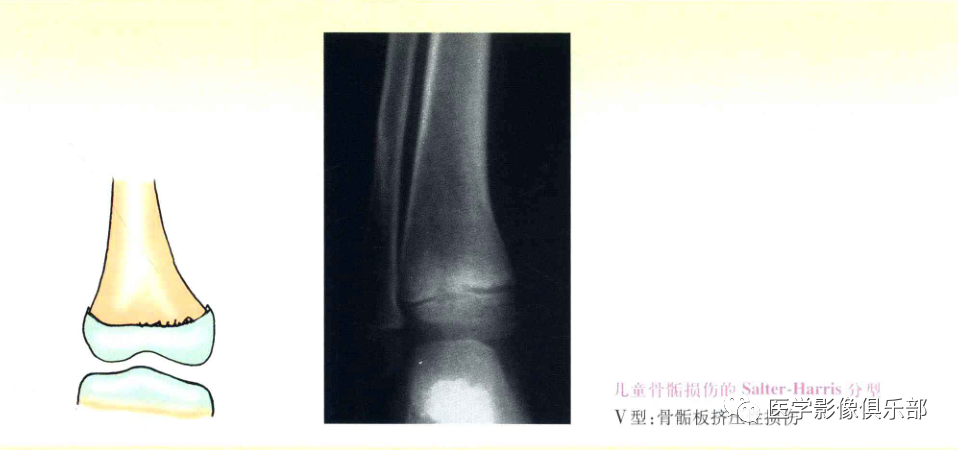

Ⅴ型:骨骺板挤压性损伤。